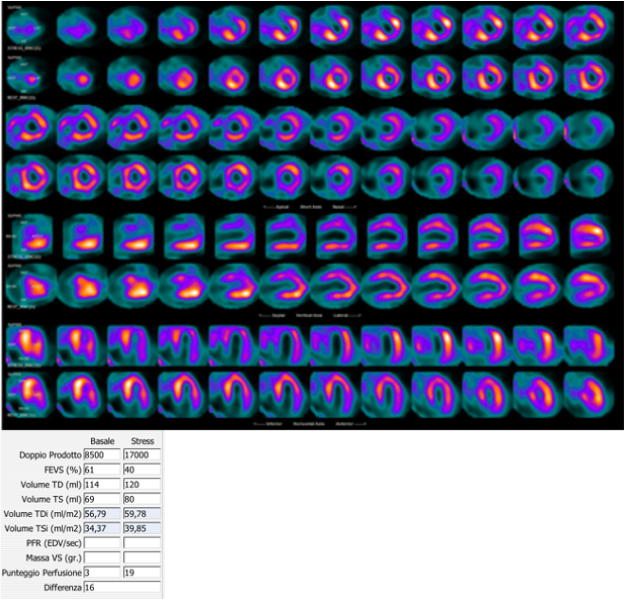

Fig. 1.99mTc-tetrofosmin cardiac SPECT with cadmium, zinc, tellurium (CZT) technology images of a 72-year-old woman with multiple cardiovascular risk factors symptomatic for typical effort angina. Perfusion SPECT revealed a reversible defect in the apex, septal, and anterior walls. Functional data showed an increase in left ventricular end-diastolic volume and end-systolic volume after stress compared to rest (120 versus 114 mL and 80 versus 69 mL, respectively); global systolic function was reduced after stress normal at rest (ejection fraction 40 versus 61%), compatible with myocardial stunning.